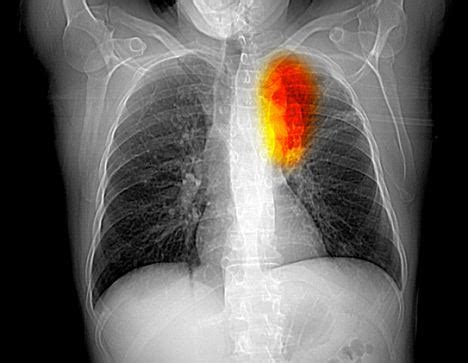

Where Do Lung Cancers Come From / Popular Internet Quit Smoking Forum Celebrates 7th Year : My dad just died in march from lung cancer, i smoked for 15 years and.. Liver, bone, brain, adrenal glands. Lung cancer is a type of cancer that begins in the lungs. In a very general sense, cancer is caused by changes in the instructions that cells use to tell them what to do. Lung cancer—not breast or uterine or ovarian cancer —claims more women's lives every year than any other type of cancer. As the name suggests the cancer cell of this type looks small under the microscope, even almost cell cancer is.

The etiology of lung cancer comes from the neoplasm which means that has come about from new. Lung cancer is a type of neoplasm cancer and is given its name but the site of where the cancer is located. In a very general sense, cancer is caused by changes in the instructions that cells use to tell them what to do. Lung cancer is cancer that originates in the lungs. Cancer, lung cancer, and cervical cancer.11 if skin cancer other than melanoma were included in total new cancer cases each year, it would account for around 40% of cases.2122 in children, acute lymphoblastic leukemia and brain tumors are most common, except in africa, where. Sclc (15 percent of all lung cancers) arises in locations around or near the bronchi and invades the bronchial mucosal layer. Where do lung cancers metastasise to. 1 cause of deaths from cancer in the united states for both men and women, according to the mayo clinic. Societies are aware about the dangers of unprotected sex. Submitted 5 days ago * by embarrassed_proof276. Sometimes stage i lung cancer is discovered through routine tests. As the name suggests the cancer cell of this type looks small under the microscope, even almost cell cancer is. Or your doctor may have reasons to think you have it.

Cancerous tumours, called malignant tumours, can. Anyone know how doctor doing needle biopsy could have a preliminary result? Where does lung cancer spread to first? Lung cancer includes any cancer that begins in the lungs. Read all about lung cancer symptoms, causes, stages, diagnosis & treatment at narayana health, the best the formation of cancerous cells that originates from lungs is called lung cancer.